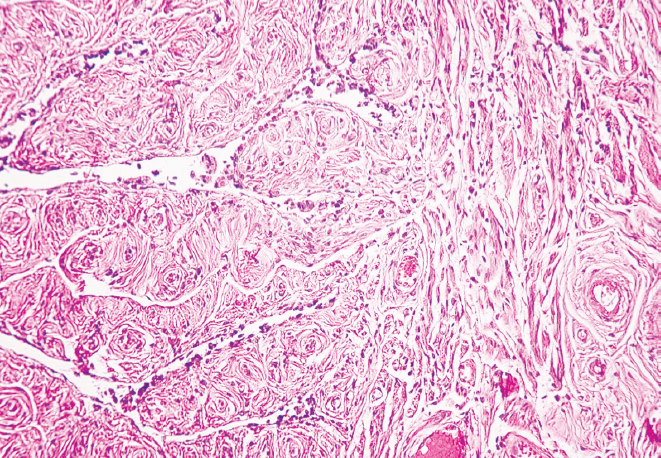

Материалы и методы. Исследование выполнено на секционном материале 70 рожавших женщин, которых разделили на две группы: в первую группу включили 34 женщины молодого возраста (22–35 лет), во вторую группу — 36 женщин старческого возраста (75–88 лет). Определяли наружный диаметр перешейка и воронки маточных труб. Для гистологического исследования изъятые при аутопсии фрагменты маточных труб в местах перешейка и воронки окрашивали пикрофуксином по Ван Гизону и гематоксилином и эозином.

Результаты. Установлено уменьшение показателей наружного диаметра перешейка и воронки обеих маточных труб женщин от молодого возраста к старческому (p < 0,01). В старческом возрасте определено преобладание параметров наружного диаметра перешейка и воронки правой маточной трубы в сравнении с показателями левой маточной трубы (p < 0,01), наряду с этим в молодом возрасте выявлена лишь тенденция к превалированию значений диаметра перешейка и воронки правой маточной трубы (p > 0,05). Гистологическое исследование показало наличие утолщенных складок слизистой оболочки и уплощенного эпителия в исследуемых областях у женщин старческого возраста, истончение слоев мышечной оболочки и разрастание соединительной ткани в сравнении с образцами, взятыми для исследования у женщин молодого возраста.

Заключение. Морфологическая перестройка перешейка и воронки маточных труб от молодого к старческому возрасту заключается в утолщении складок слизистой оболочки, уплощении эпителия, разрастании соединительной ткани в стенке и уменьшении их наружного диаметра с преобладанием параметров в правой маточной трубе.